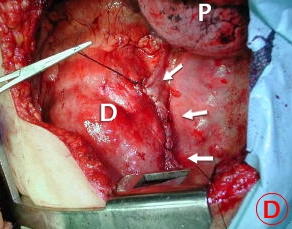

Toracotomía Izquierda

Fotografía A:

El contenido herniado intra-torácico, toracotomía postero lateral Izquierda en 6To. espacio Intercostal

Fotografía B:

a - Intestino delgado dilatado y violáceo

P (azul) - Pulmón, lóbulo superior ventilándose

P (blanca) - Lóbulo pulmonar inferior atelectasiado.

El contenido herniado liberado de las adherencias pulmonares y pleurales. Observe el aspecto de la pared de las asas intestinales, posteriormente mejoró su irrigación y el color de las mismas.

Flechas - El anillo herniario o agujero diafragmático suturado, una vez incorporado al abdomen el contenido herniado y liberado de sus adherencias.

P - Pulmón